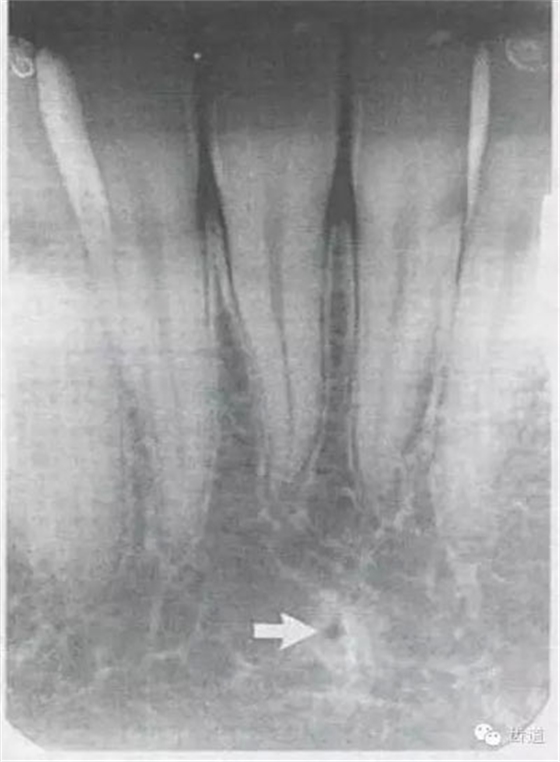

1)頦棘:

位于兩下中切牙根尖下方,下頜骨正中聯(lián)合處顯示為小圓形密度高的影像,在中心有點(diǎn)狀密度低的影像,其周圍骨小梁稀少,為骨松質(zhì)區(qū)。

2)營(yíng)養(yǎng)管:

常見(jiàn)于下頜前牙區(qū),在牙根之間的牙槽骨內(nèi)并與牙長(zhǎng)軸平行的密度低的條狀影像。此為小血管進(jìn)入牙槽突的影像。